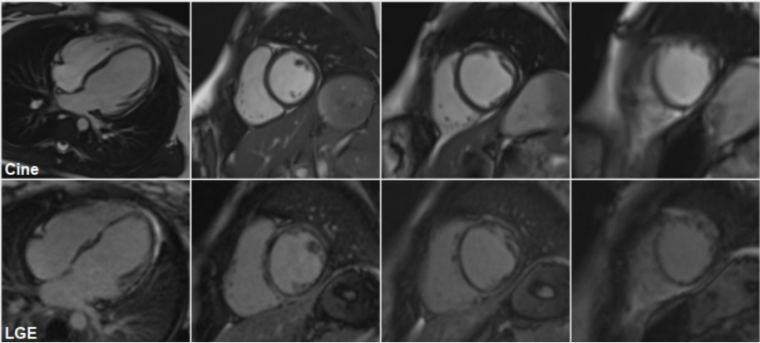

A repeat cardiac MRI was performed on March 2023 (figure 3):

This confirmed the presence of left ventricular dilatation (LVEDV 101 mL/m2, z+2.6; LVESV 57 mL/m2, z+6.4) with reduced global systolic function (LVEF 43%).  There was thinning of the apical segments and regional wall motion abnormalities, affecting in particular the mid cavity to apical septum and the apical anterior wall.  The left atrium was not dilated.  There was extensive subepicardial and mid wall LGE in a nonischaemic pattern, involving the inferior, lateral, anterior wall and septum with an almost circumferential ring-like appearance at the base mid cavity, extending to the apical segments.  RV volumes were again normal with preserved global systolic function.